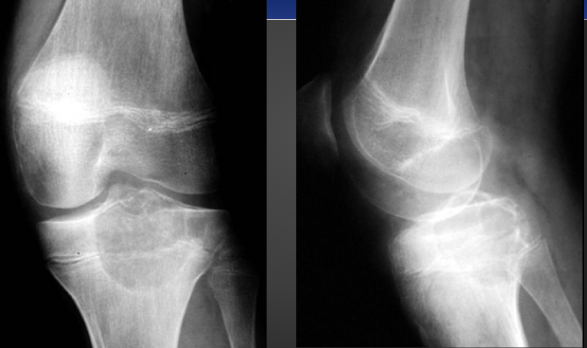

Giant Cell Tumor

-AKA Osteoclastoma

-Quasi malignant (80% benign, 5-8% of primary malignancies, 15% of benign osseous neoplasms)

-Most common at 20 to 40 years of age

Giant Cell common locations

-Knee (most common)

-Distal radius

-Proximal humerus

-Sacrum

Imaging Feature of Giant Cell Tumor

-Geographic lytic lesion eccentrically located within the metaphysis about the knee, without a sclerotic margin

-In long bone 90% will have subarticular extension

-80 to 90% will not show sclerotic margin

-Multiloculate and septated

-Expansile

-Imaging cannot differentiate malignant from benign

Giant Cell Tumor on X-ray